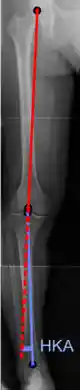

![]()

Hip-knee-ankle angle.

There are two disorders relating to an abnormal angle in the coronal plane at the level of the knee:

- Genu valgum is a valgus deformity in which the tibia is turned outward in relation to the femur, resulting in a knock-kneed appearance.

- Genu varum is a varus deformity in which the tibia is turned inward in relation to the femur, resulting in a bowlegged deformity.

The degree of varus or valgus deformity can be quantified by the hip-knee-ankle angle,[25] which is an angle between the femoral mechanical axis and the center of the ankle joint.[26] It is normally between 1.0° and 1.5° of varus in adults.[27] Normal ranges are different in children.[28]